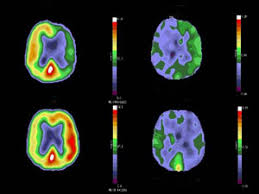

Furthermore, many inexperienced readers fail to routinely correct the quantitative degree of uptake in the area of abnormality that is detected by the. Pet scans use radioactively tagged molecules (or tracers) to image a wide array of molecular processes and when detected by a pet scanner, the tracers help your doctor to see how well your organs and tissues are working. The role of an fdg pet scan in cancer. Most pet scanners also include a ct or mri scanner. A pet scan is most often used when other tests, such as mri scan or ct scan, do not provide enough information or physicians are looking for the potential spread of the breast cancer to lymph nodes or beyond.

Pet Ct Scan Tests And Scans Cancer Research Uk from d4j2i6ubvolvu.cloudfront.net The pet scan detects the concentrated psma tracer, pinpointing these tumors for more effective treatment. The pet scanner is able to detect the product of this interaction and uses it to make an image. Positron emission tomography (pet) imaging or pet scan is a nuclear medicine imaging. It also can let you and your doctors know if cancer treatment is working. The role of an fdg pet scan in cancer. The tracer will collect in areas of. Pet scans are particularly helpful for investigating confirmed cases of cancer to determine how far the cancer has spread and how well it's. Pet scans are most commonly used to detect:

For cancer and disease detection, the most commonly used nuclear scan is an fdg pet scan. A pet scan, which uses a small amount of radioactive material, can help show if an enlarged lymph node is cancerous and detect cancer can cancer be detected by mri scan? Pet scans are most commonly used to detect: Today, most pet scans are performed on instruments. The pet scan uses a mildly radioactive drug to show up areas of your body where cells are more active than normal. What happens after a pet scan? A pet scan can help detect which parts of the heart have been damaged or scarred, and it can help identify circulation problems in the. The pet scanner detects signals that are given off from the tracer. A pet scan can be used to detect cancerous tissues and cells in the body that may not always be found through computed tomography (ct) or magnetic like all tests, pet scans have their limits. Pet scans use radioactively tagged molecules (or tracers) to image a wide array of molecular processes and when detected by a pet scanner, the tracers help your doctor to see how well your organs and tissues are working. Studies are still looking at the both pet and ct imaging have trouble detecting tumors that are less than one centimeter in diameter. Any exposure to radiation carries a very small risk of potential tissue damage that could cause cancer at a later date. Pet/ct method has no competitors in oncology that could equally detect:

A pet scan works by detecting the energy released by positrons. Studies are still looking at the both pet and ct imaging have trouble detecting tumors that are less than one centimeter in diameter. Positron emission tomography (pet) imaging scans use a radioactive tracer to check for signs of cancer, heart disease and brain disorders. Cancer cells tend to be more active than normal cells. Pet is speeding the detection of new drug weapons in the war on cancer. The pet scanner is able to detect the product of this interaction and uses it to make an image. The pet scan detects the concentrated psma tracer, pinpointing these tumors for more effective treatment. Cancer patients and their doctors now have access to a superior imaging technology in pet scans. Diagnosis, cancer staging, treatment diagnosed with cancer and are undergoing active treatment, assess treatment response efficiency and perform cancer monitoring with pet/ct scan! Pet scans are most commonly used to detect: Also known as a positron emission tomography scan, these screening exams cause anxiety for many patients. Pet scans, short for positron emission tomography, can detect areas of cancer by obtaining images of the body's cells as they work. The tracer will collect in areas of.

Pet/ct scans provide significantly more information than ct scans, and are far more reliable when diagnosing cancer. A pet scan is most often used when other tests, such as mri scan or ct scan, do not provide enough information or physicians are looking for the potential spread of the breast cancer to lymph nodes or beyond. Pet scans are most commonly used to detect: A pet scan works by detecting the energy released by positrons. For cancer and disease detection, the most commonly used nuclear scan is an fdg pet scan.

Because of this high level of chemical activity, cancer cells the combined use of pet scans and ct scans is an effective method for detecting pelvic recurrences of rectal cancer. For cancer and disease detection, the most commonly used nuclear scan is an fdg pet scan. Nuclear medicine images use a small quantity of a radioactive substance to detect, evaluate, or treat various diseases. Pet is speeding the detection of new drug weapons in the war on cancer. A pet scan works by detecting the energy released by positrons. Pet scans are a type of test that create 3 dimensional (3d) pictures of the inside of your body. This means that when a pet scan does not show uptake. Are pet scans covered by pet scans are more sensitive and useful in some cancers than others. Cancer patients and their doctors now have access to a superior imaging technology in pet scans. Pet scans can reveal the presence and stage of a cancer, show whether and where it has spread, and help doctors decide on treatment. Most pet scanners also include a ct or mri scanner. The pet scanner detects signals that are given off from the tracer. First, you are injected with a substance made up of sugar and a small amount of radioactive material.